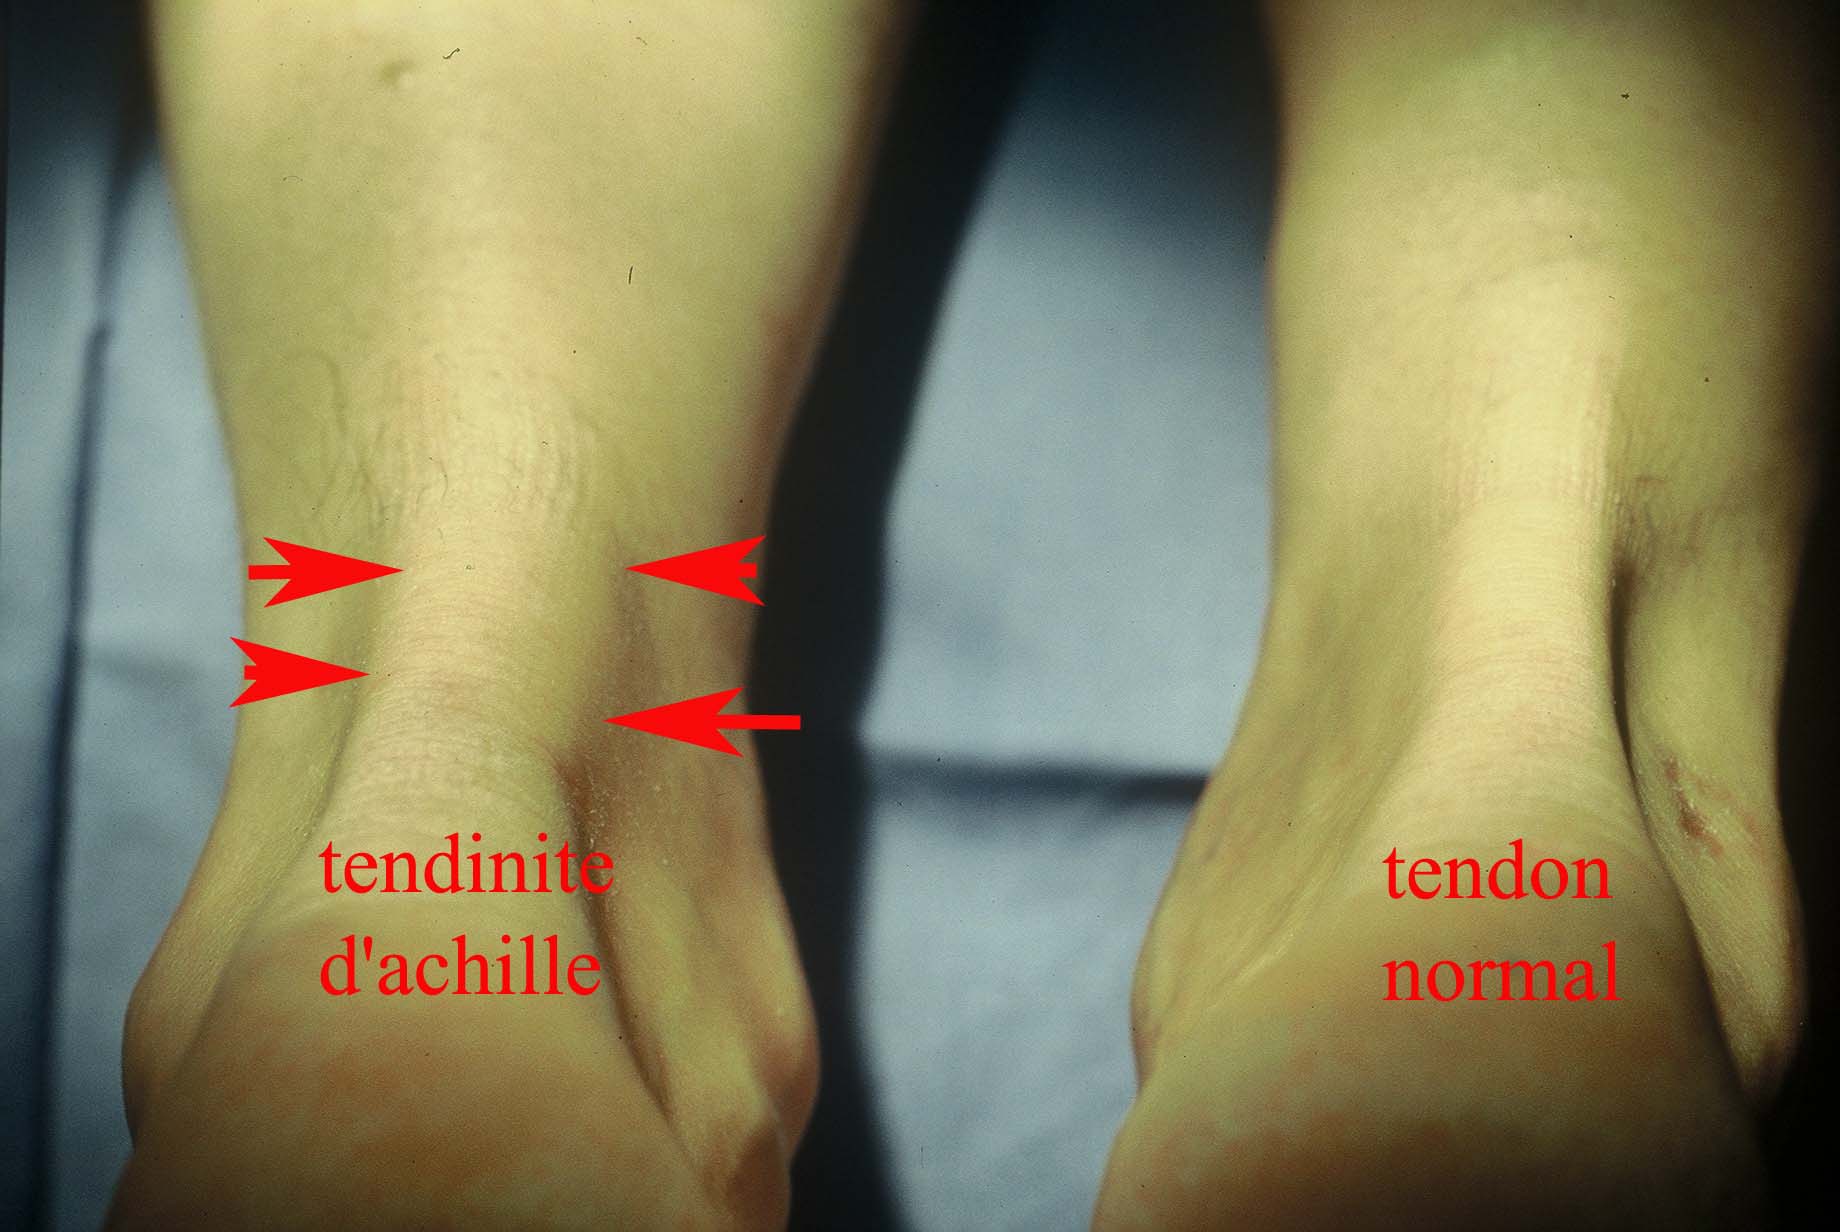

Tendinite du tendon d Achille Causes Symptomes Traitements